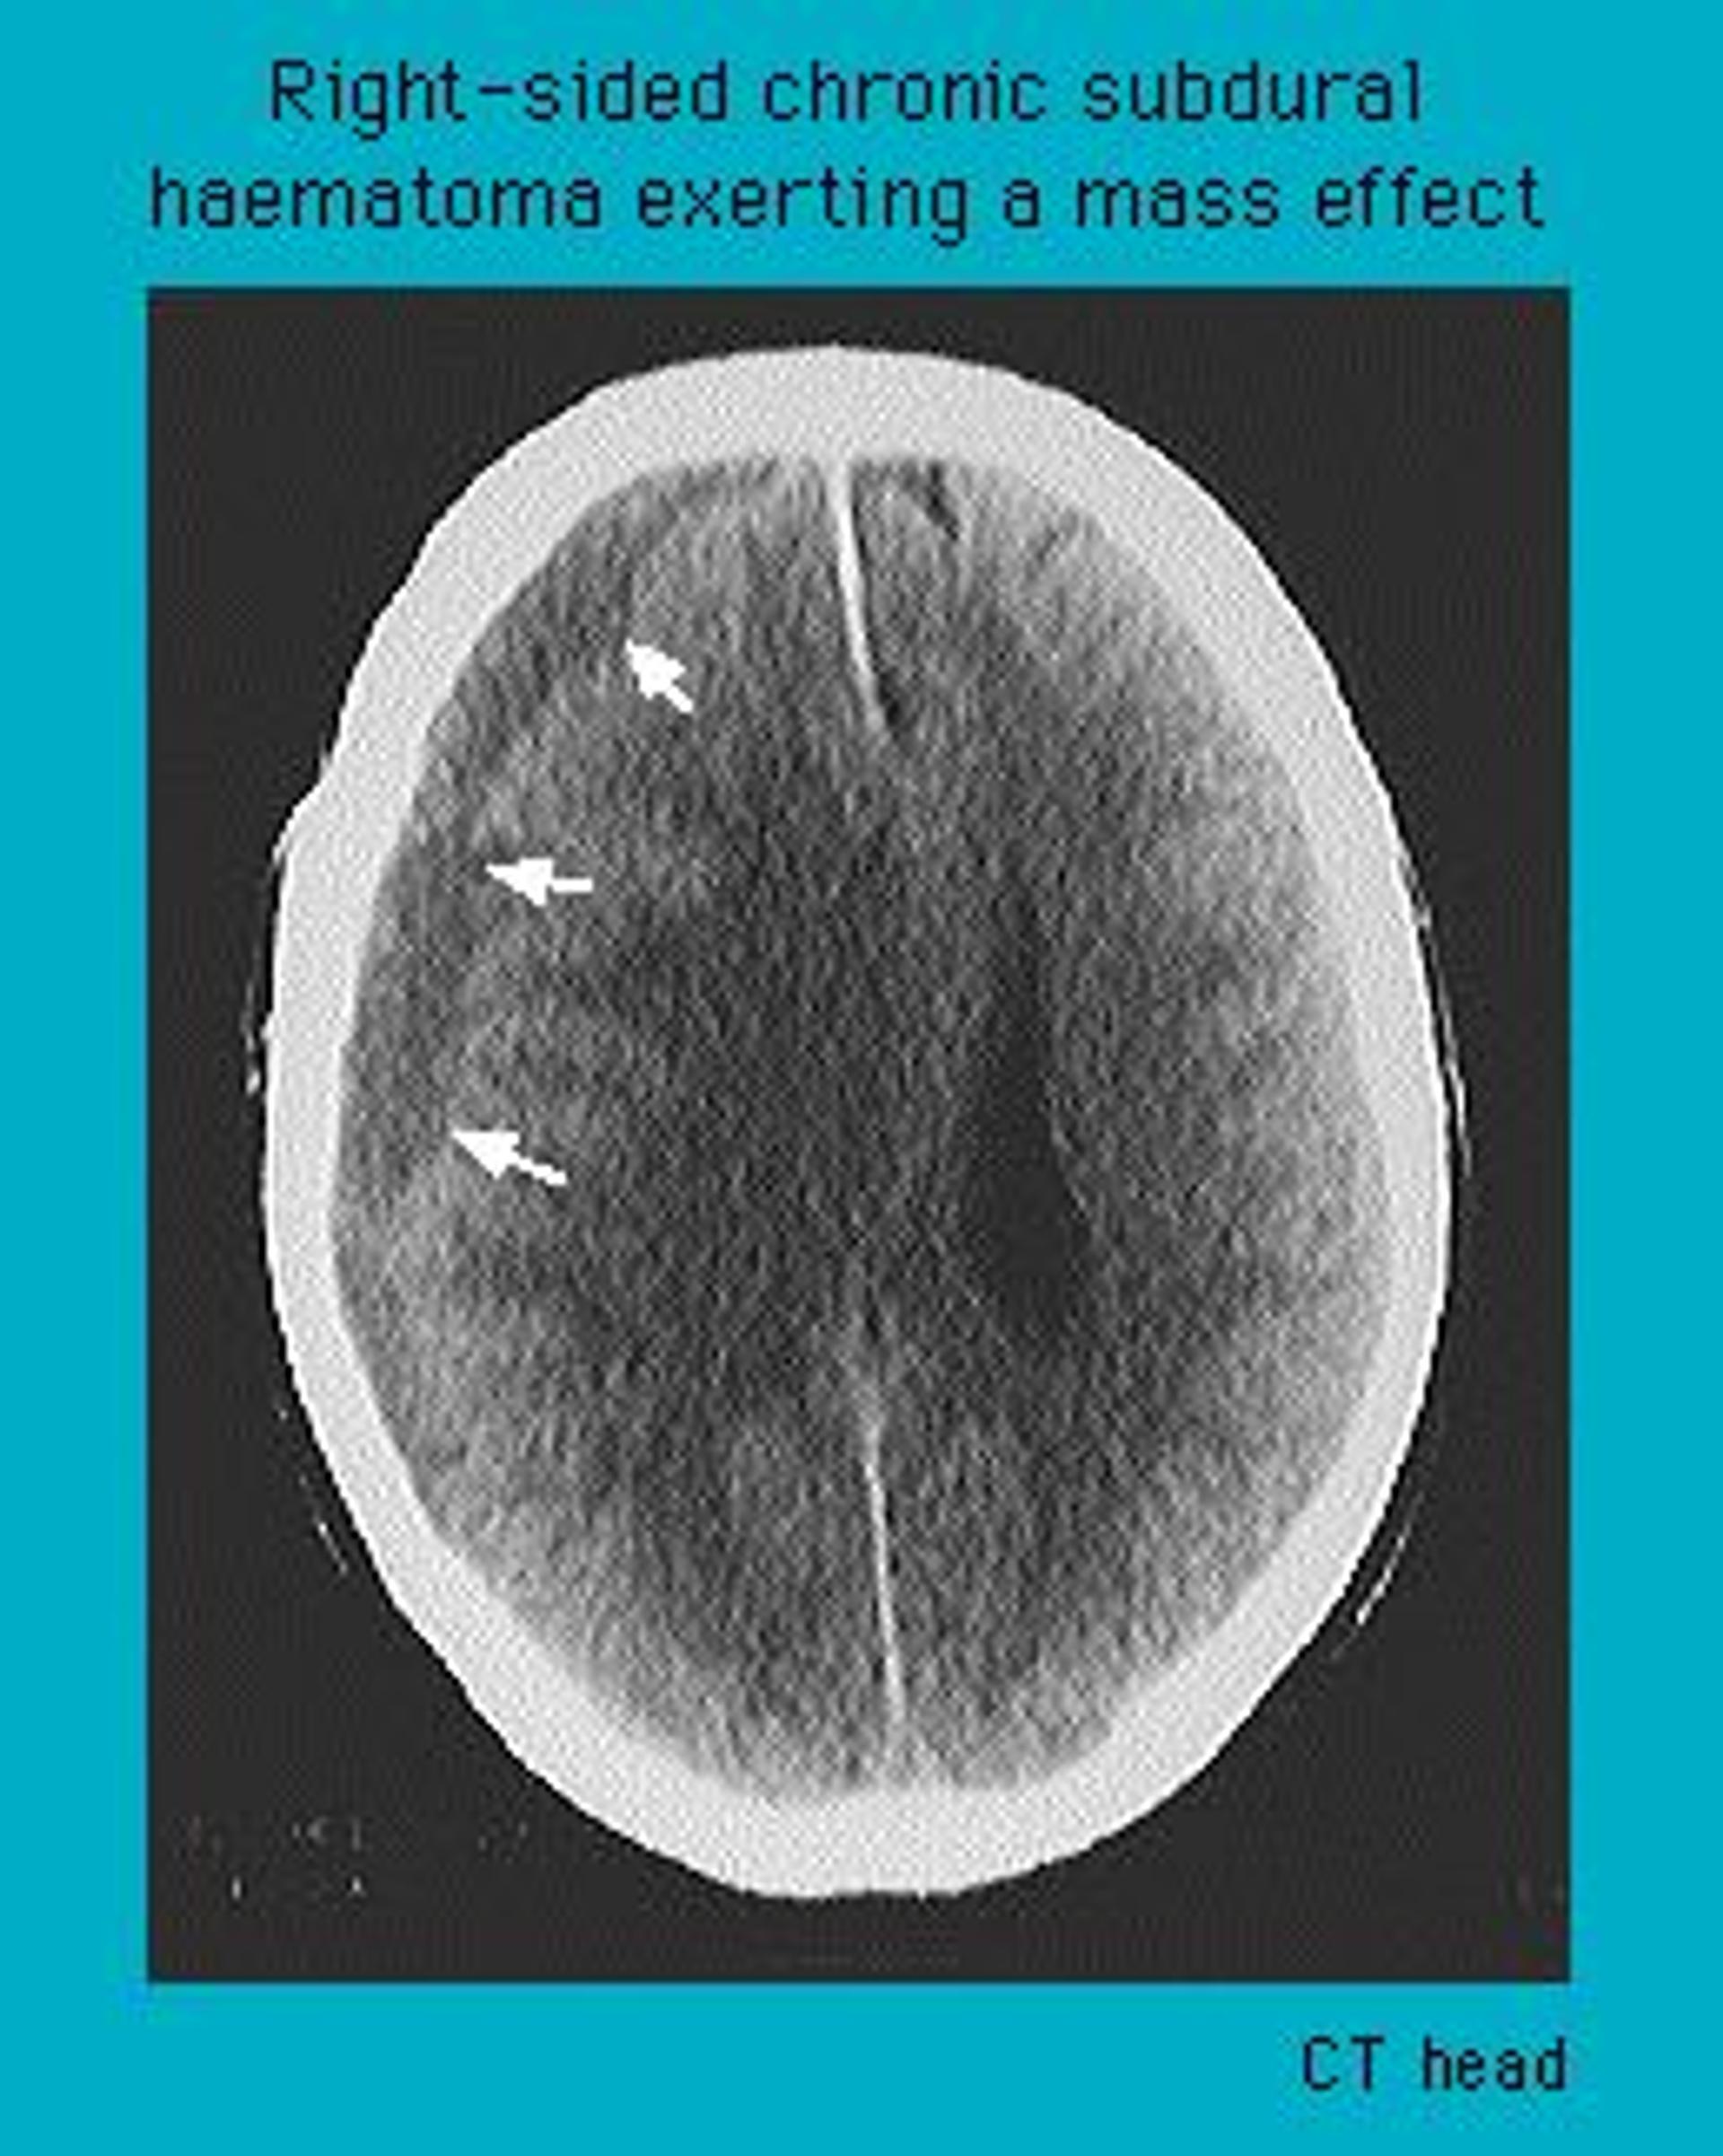

CT scan of a chronic subdural haematoma